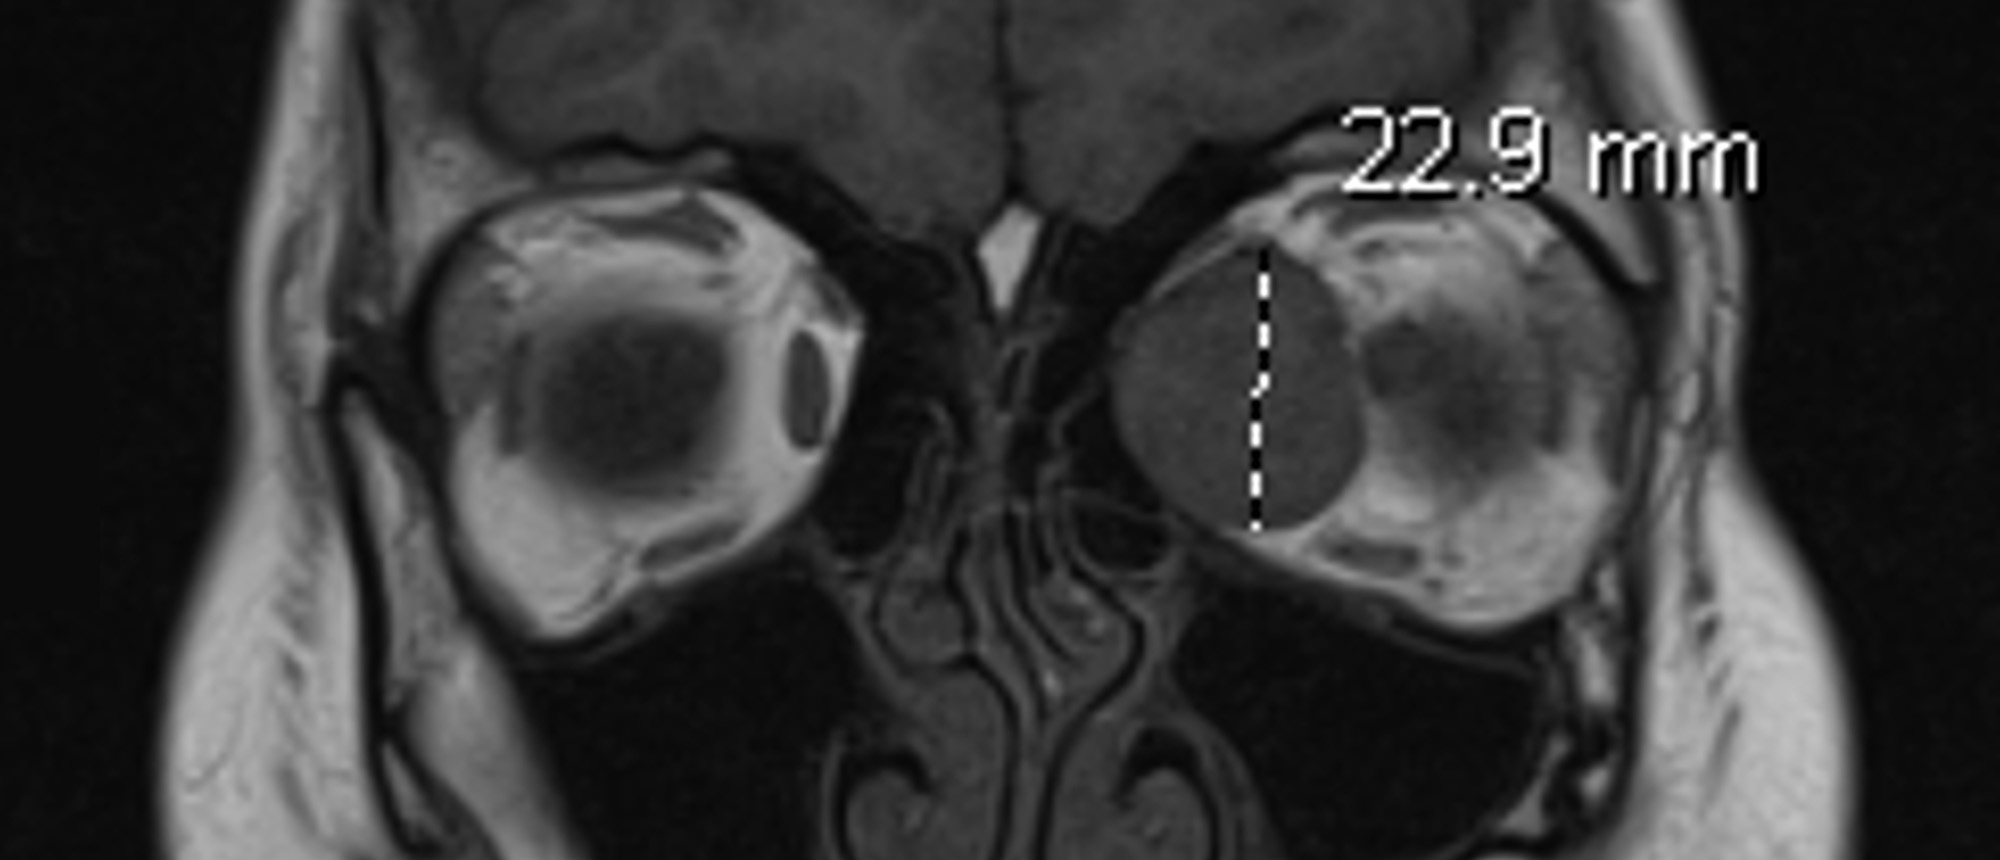

Choroidal Metastasis A patient presented to the Bascom Palmer Eye Institute with blurred vision in the left eye for 5 days. Past medical and ocular history was unremarkable. Past social history was notable for 25 pack-year smoking history. Visual acuity in the right eye was 20/20. Visual acuity in …